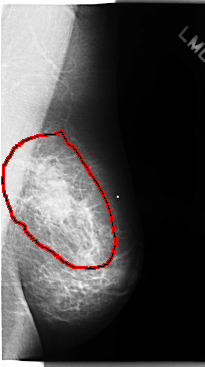

C_0108_1.LEFT_MLO

LEFT_MLO LINES 4760 PIXELS_PER_LINE 2656 BITS_PER_PIXEL 12 RESOLUTION 50 OVERLAY

FILE: C_0108_1.LEFT_MLO.OVERLAY

TOTAL_ABNORMALITIES 1

ABNORMALITY 1

LESION_TYPE MASS SHAPE IRREGULAR MARGINS ILL_DEFINED

ASSESSMENT 5

SUBTLETY 5

PATHOLOGY MALIGNANT

TOTAL_OUTLINES 1

BOUNDARY